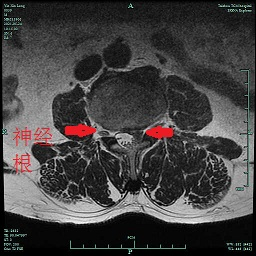

前段時間,臺州市中醫(yī)院就來了一名“腰椎間盤突出癥”患者。59歲的尹先生自訴有“腰椎間盤突出癥”病史10余年,住院前3天突然出現(xiàn)明顯的左側(cè)腰腿痛,久坐或走路時疼痛劇烈,難以忍受,“感覺自己左側(cè)大腿內(nèi)側(cè)的肉都是死的,一點感覺都沒有,會不會癱瘓了?”這可把尹先生嚇得不輕,以為自己是中風(fēng)了,馬上入住了醫(yī)院神經(jīng)內(nèi)科,后來做了腰椎磁共振,MR提示:腰3∕4椎間盤向上脫垂,壓迫相應(yīng)節(jié)段左側(cè)神經(jīng)根。經(jīng)骨科顏峰主任會診后,轉(zhuǎn)入骨科擬行“椎間孔鏡下髓核摘除術(shù)”。

5月28日,顏峰主任順利地為尹先生實施了“椎間孔鏡下腰3∕4脫出髓核摘除術(shù)”,術(shù)中取出一塊完整的髓核,術(shù)后即刻患者腰腿痛、大腿內(nèi)側(cè)的麻木基本消失。